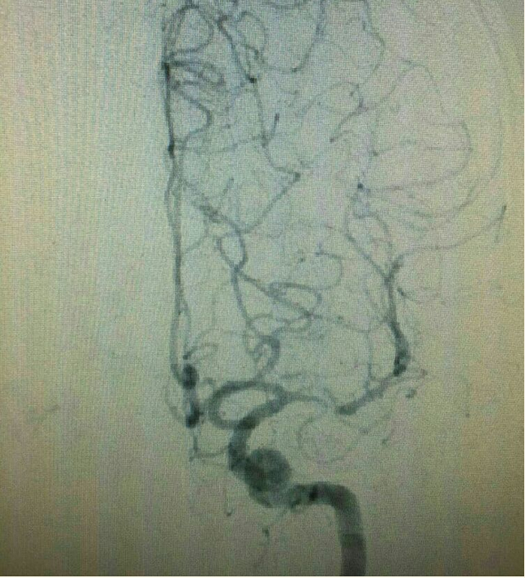

出院1月后再次出现右侧肢体无力,并反应迟钝,行脑血管造影见左侧大脑中动脉重度狭窄。

给予双抗(氯吡格雷联合阿司匹林)治疗3周,症状无明显改善,复查造影见左大脑中远端血流较前明显变差。